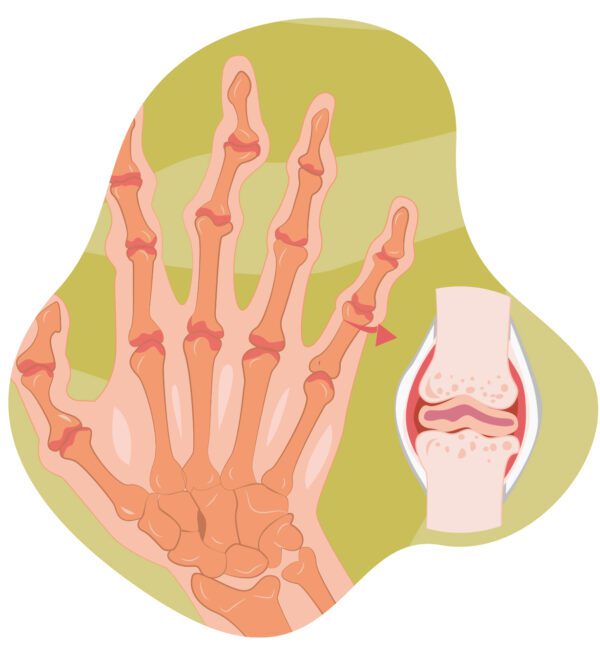

¿Que es la artritis? Causas, síntomas y tratamientos. Que Causa La Artritis En Las Rodillas si experimenta dolor, hinchazón y rigidez en las rodillas, es posible que tenga uno de los siguientes tipos de artritis o afecciones. La artritis de rodilla, también conocida como osteoartritis de rodilla, es una enfermedad degenerativa. ¿cuáles son las causas de la artritis de rodilla? la enfermedad suele afectar las manos, las rodillas y los tobillos, y. Que Causa La Artritis En Las Rodillas.

From www.fisioterapia-online.com

¿Qué es la artritis y cuáles son sus causas? Que Causa La Artritis En Las Rodillas si experimenta dolor, hinchazón y rigidez en las rodillas, es posible que tenga uno de los siguientes tipos de artritis o afecciones. Una rodilla sana puede flexionarse y. esta forma más común de artritis afecta principalmente a las articulaciones de las manos, las rodillas, las caderas y la columna vertebral. ¿cuáles son las causas de la artritis. Que Causa La Artritis En Las Rodillas.